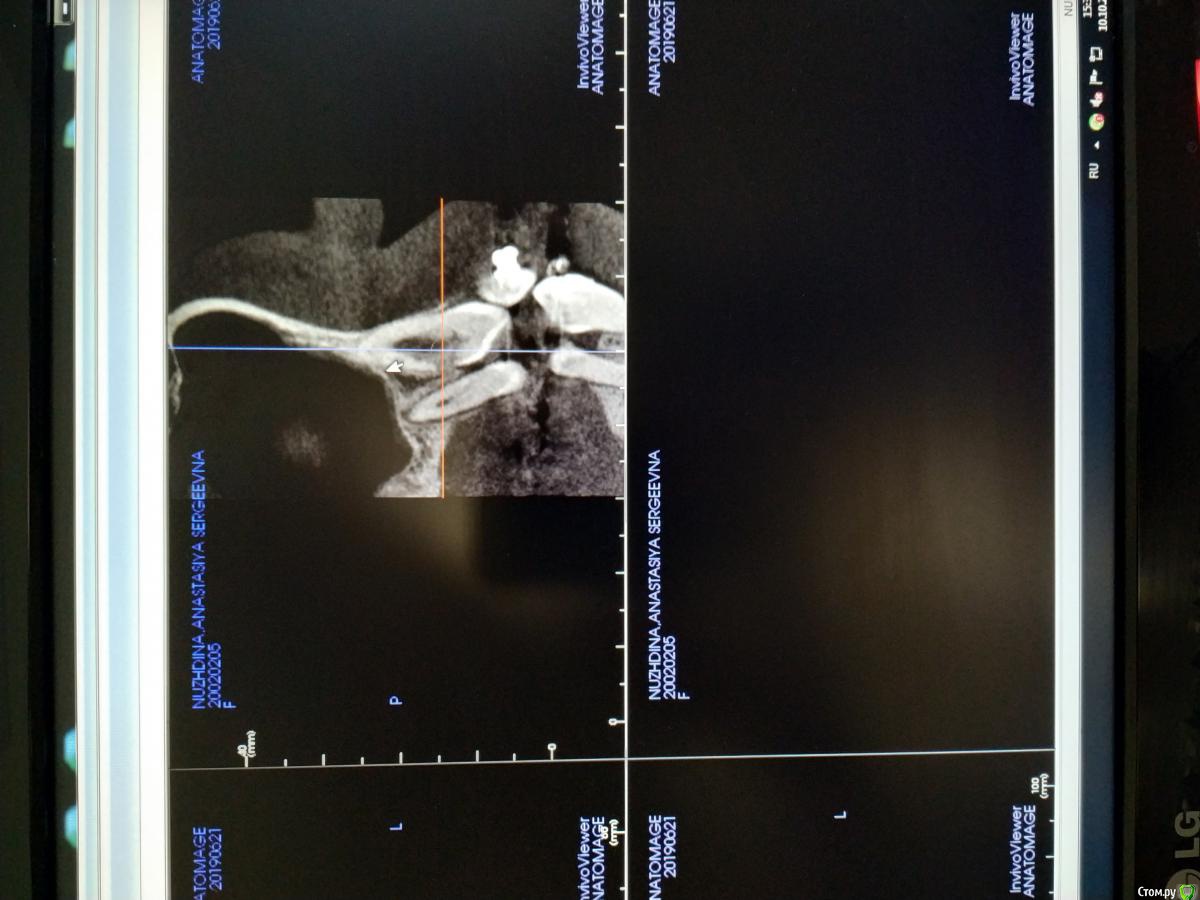

Здравствуйте. Ситуация такая: Ортодонт проводила лечение пациентки около года или немного больше, при попытке вытянуть клык соседние зубы наоборот стремились к клыку. В итоге был сделан 3Д снимок, фото прилагаю. Пациентка была только на консультации, лечится в др клинике.

Там ей предложили депульпировать и протезирование, но как я понимаю в зуб "врастает" костная ткань, соответственно после депульпирования есть риск получить просто резорбцию.

Возможно ли сделав остеоперфорацию в данной области ослабить сообщение с костной тканью, вытянуть зуб и уже потом депульпировать и запротезировать, когда зона риска будет над уровнем кости?